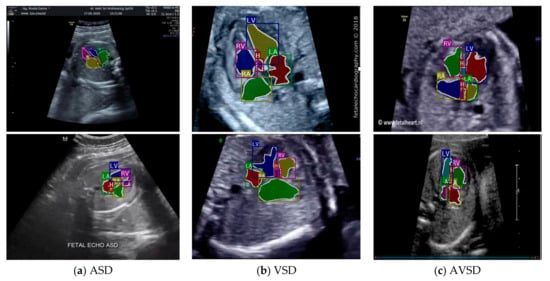

We also conducted heart chamber segmentation and detection in 4CH view with abnormal anatomy image. The fetal heart chamber prediction with the proposed model is presented in Figure 13. This experimental result differed from the IoU and DCS performance in Figure 11, as the fetal heart images are taken from the patients with CHDs. The experiment was conducted based on intra- and inter-patient data. The RoI was a segment of four object classes, namely, LA, LV, RA, and RV. With the use of the Mask-RCNN model, all classes can be segmented and classified in the three conditions. Overall performances show that intra-patient data allowed better IoU and DCS performance compared with inter-patient data.

Figure 13.

The performance in fetal heart chamber segmentation in 4CH view based on intra- and inter-patient scenario: (a) IoU and (b) DCS.

As shown in Figure 13a,d, the proposed model produced satisfactory results, with a large overlap between the ground truth and the predicted image. All IoU values exceeded the baseline of 0.5, which is the gold standard value for ensuring that all processes can be run with good performance. The IoU and DCS performances with the intra-patient data were better than those with the inter-patient data, with scores of above 66.37% and 79.60%, respectively. The performance with the inter-patient data was poorer than that with the intra-patient data. Due to the inherent differences in appearance across different imaging modalities, it is challenging to construct accurate image similarity measures. As the underlying anatomical components vary between patients, inter-patient registration might be difficult. In future work, the detection performance for the inter-patient scenario should be enhanced. The image sample for the heart chamber with a heart defect can be seen in Figure 14 with the defect position marked in red and blue. In this detection process, the defect can be small or large, depending on its severity. However, in this study, the defect size parameter was not taken into account; for further research, it will be very important to diagnose the severity of the condition.

Figure 14.

The sample result of wall-chamber segmentation with 4 CH view in ASD, VSD, and AVSD condition based on abnormal anatomy structure.